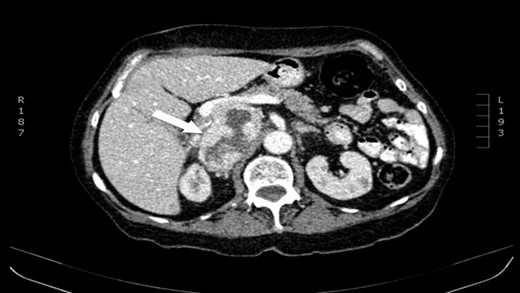

The authors report a case of a 64-year-old female, with no relevant family history and a past medical history of recently diagnosed supraventricular tachycardia, arterial hypertension, type 2 diabetes mellitus, euthyroid multinodular goiter and chronic venous insufficiency. She was referred to our Institution from other Hospital where she went due to paroxysms of palpitations, headache and diaphoresis, that led to biochemical investigation that was remarkable for: total plasmatic cathecolamines: 73 747 ng/L (normal range (NR) <598 ng/L), plasmatic noradrenaline: 73 589 ng/L (NR <420 ng/L), adrenaline: 130 ng/L (NR <84 ng/L), plasmatic dopamine: 28 ng/L (NR <94ng/L), aldosterone: 87,5 ng/dL (NR 4–31 ng/dL), plasmatic renin activity: 33 ng/mL/h (NR 0,5–4 ng/mL/h), Vanylmandelic acid: 39,2 mg/24 h (NR <13,6 mg/24 h). Abdominal contrast enhanced CT scan revealed a large (70 × 35×78 mm3), hyperdense (20 HU) right adrenal mass. Abdominal magnetic resonance (MRI) also described an adrenal mass with 66×33 mm2, suggestive of pheocromocitoma (slightly hypointense on T1 and markedly hyperintense on T2 weighted imaging). No vascular nor locoreginal lymph node involvement were found and the left adrenal was radiologically normal. The patient underwent genetic testing with next generation sequencing, that excluded mutations of the succinate dehydrogenase (SDHB, C, D and A), MEN2, VHL, Neurofibromatosis type 1 genes. Genetic testing for MAX and TMEM127 were not performed due to institutional unavailability. Pre-operative pharmacological therapy was initiated with phenoxybenzamine (10 mg twice a day), followed by bisoprolol (20 mg/day) and amlodipine (5 mg/day), which rendered the patient fit for surgery. The patient underwent transperitoneal laparoscopic right adrenalectomy. Intraoperatively, a hipervascularized right adrenal gland with adhesions to the upper pole of the kidney was identified and excised, with no complications recorded. In the immediate post-operative period, antihypertensive drugs were stopped and blood pressure remained normal until the second post-operative day, when hypertension and tachycardia recurred, leading to urinary metanephrine reevaluation on the 10th post-operative day. The results were highly suggestive of disease persistence (urinary normetanephrines >10 500 ng/L (NR <600 ng/L)). Histology revealed no signs of neoplasia. Abdominal CT scan revealed the persistence of a solid heterogeneous nodule, with 70 × 49 × 87 mm3 (AP × T × L) adjacent to upper right renal pole, with peripheral contrast enhancement and central necrosis (Figs 1–3). This findings suggested abdominal paraganglioma (of the organ of Zuckerkandl). Due to the higher malignant potential of paragangliomas, an 123I-MIBG scintigraphy was performed, excluding metastatic disease.

CT scan (axial) of the heterogenous solid nodule with 70 × 49 × 87 mm3 with peripheral contrast enhancement and central necrosis (white arrow).